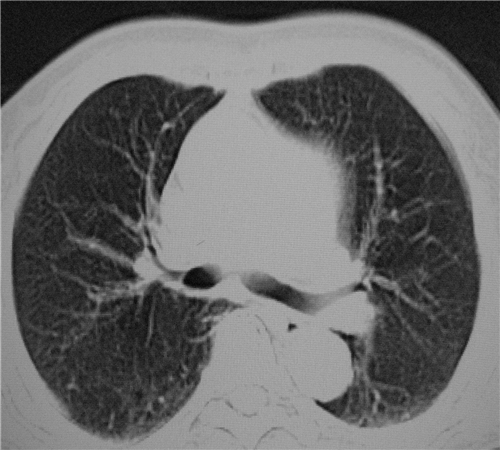

标题: CT26849:女67岁反复胸痛两天余,临床考虑夹层。 [打印本页]

标题: CT26849:女67岁反复胸痛两天余,临床考虑夹层。

右肺感染,未见夹层。

既然考虑夹层,建议强化!另:右下肺感染!

1)右肺感染性病变。2)建议行ct增强扫描或mri检查排除主动脉夹层。

双下肺感染,右侧显著。有无夹层,增强扫描后再诊断。

1. 感染性病变,2.未见夹层,3.食道未见异常。